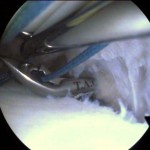

3. Mosaicoplastia para defectos del cartílago

Desde hace muchos años, venimos desarrollando esta técnica para defectos focales del cartílago. Con ella logramos restituir no sólo el cartílago sino también el hueso subcentral, es decir, lo que a nosotros nos gusta denominar «unidad osteocondral». Utilizamos injertos tomados de la propia rodilla del paciente (zona donante) que se insertan en el área dañada. Es la técnica de elección en deportistas de alta demanda (fútbol, baloncesto, pádel, etc) con unos resultados de vuelta al deporte por encima de otras técnicas como el cultivo de condrocitos o las microfracturas. Se utiliza sobre todo en rodilla pero también la hemos empleado para lesiones de tobillo (astrágalo) y hombro. A continuación, mostramos varios casos de mosaicoplastia

- mosaicoplastia abierta

- Mosaicoplastia + sutura de menisco

- Mosaicoplastia con 3 cilindros osteocondrales en cóndilo femoral

- Mosaicoplastia artroscópica de rótula según técnica personal